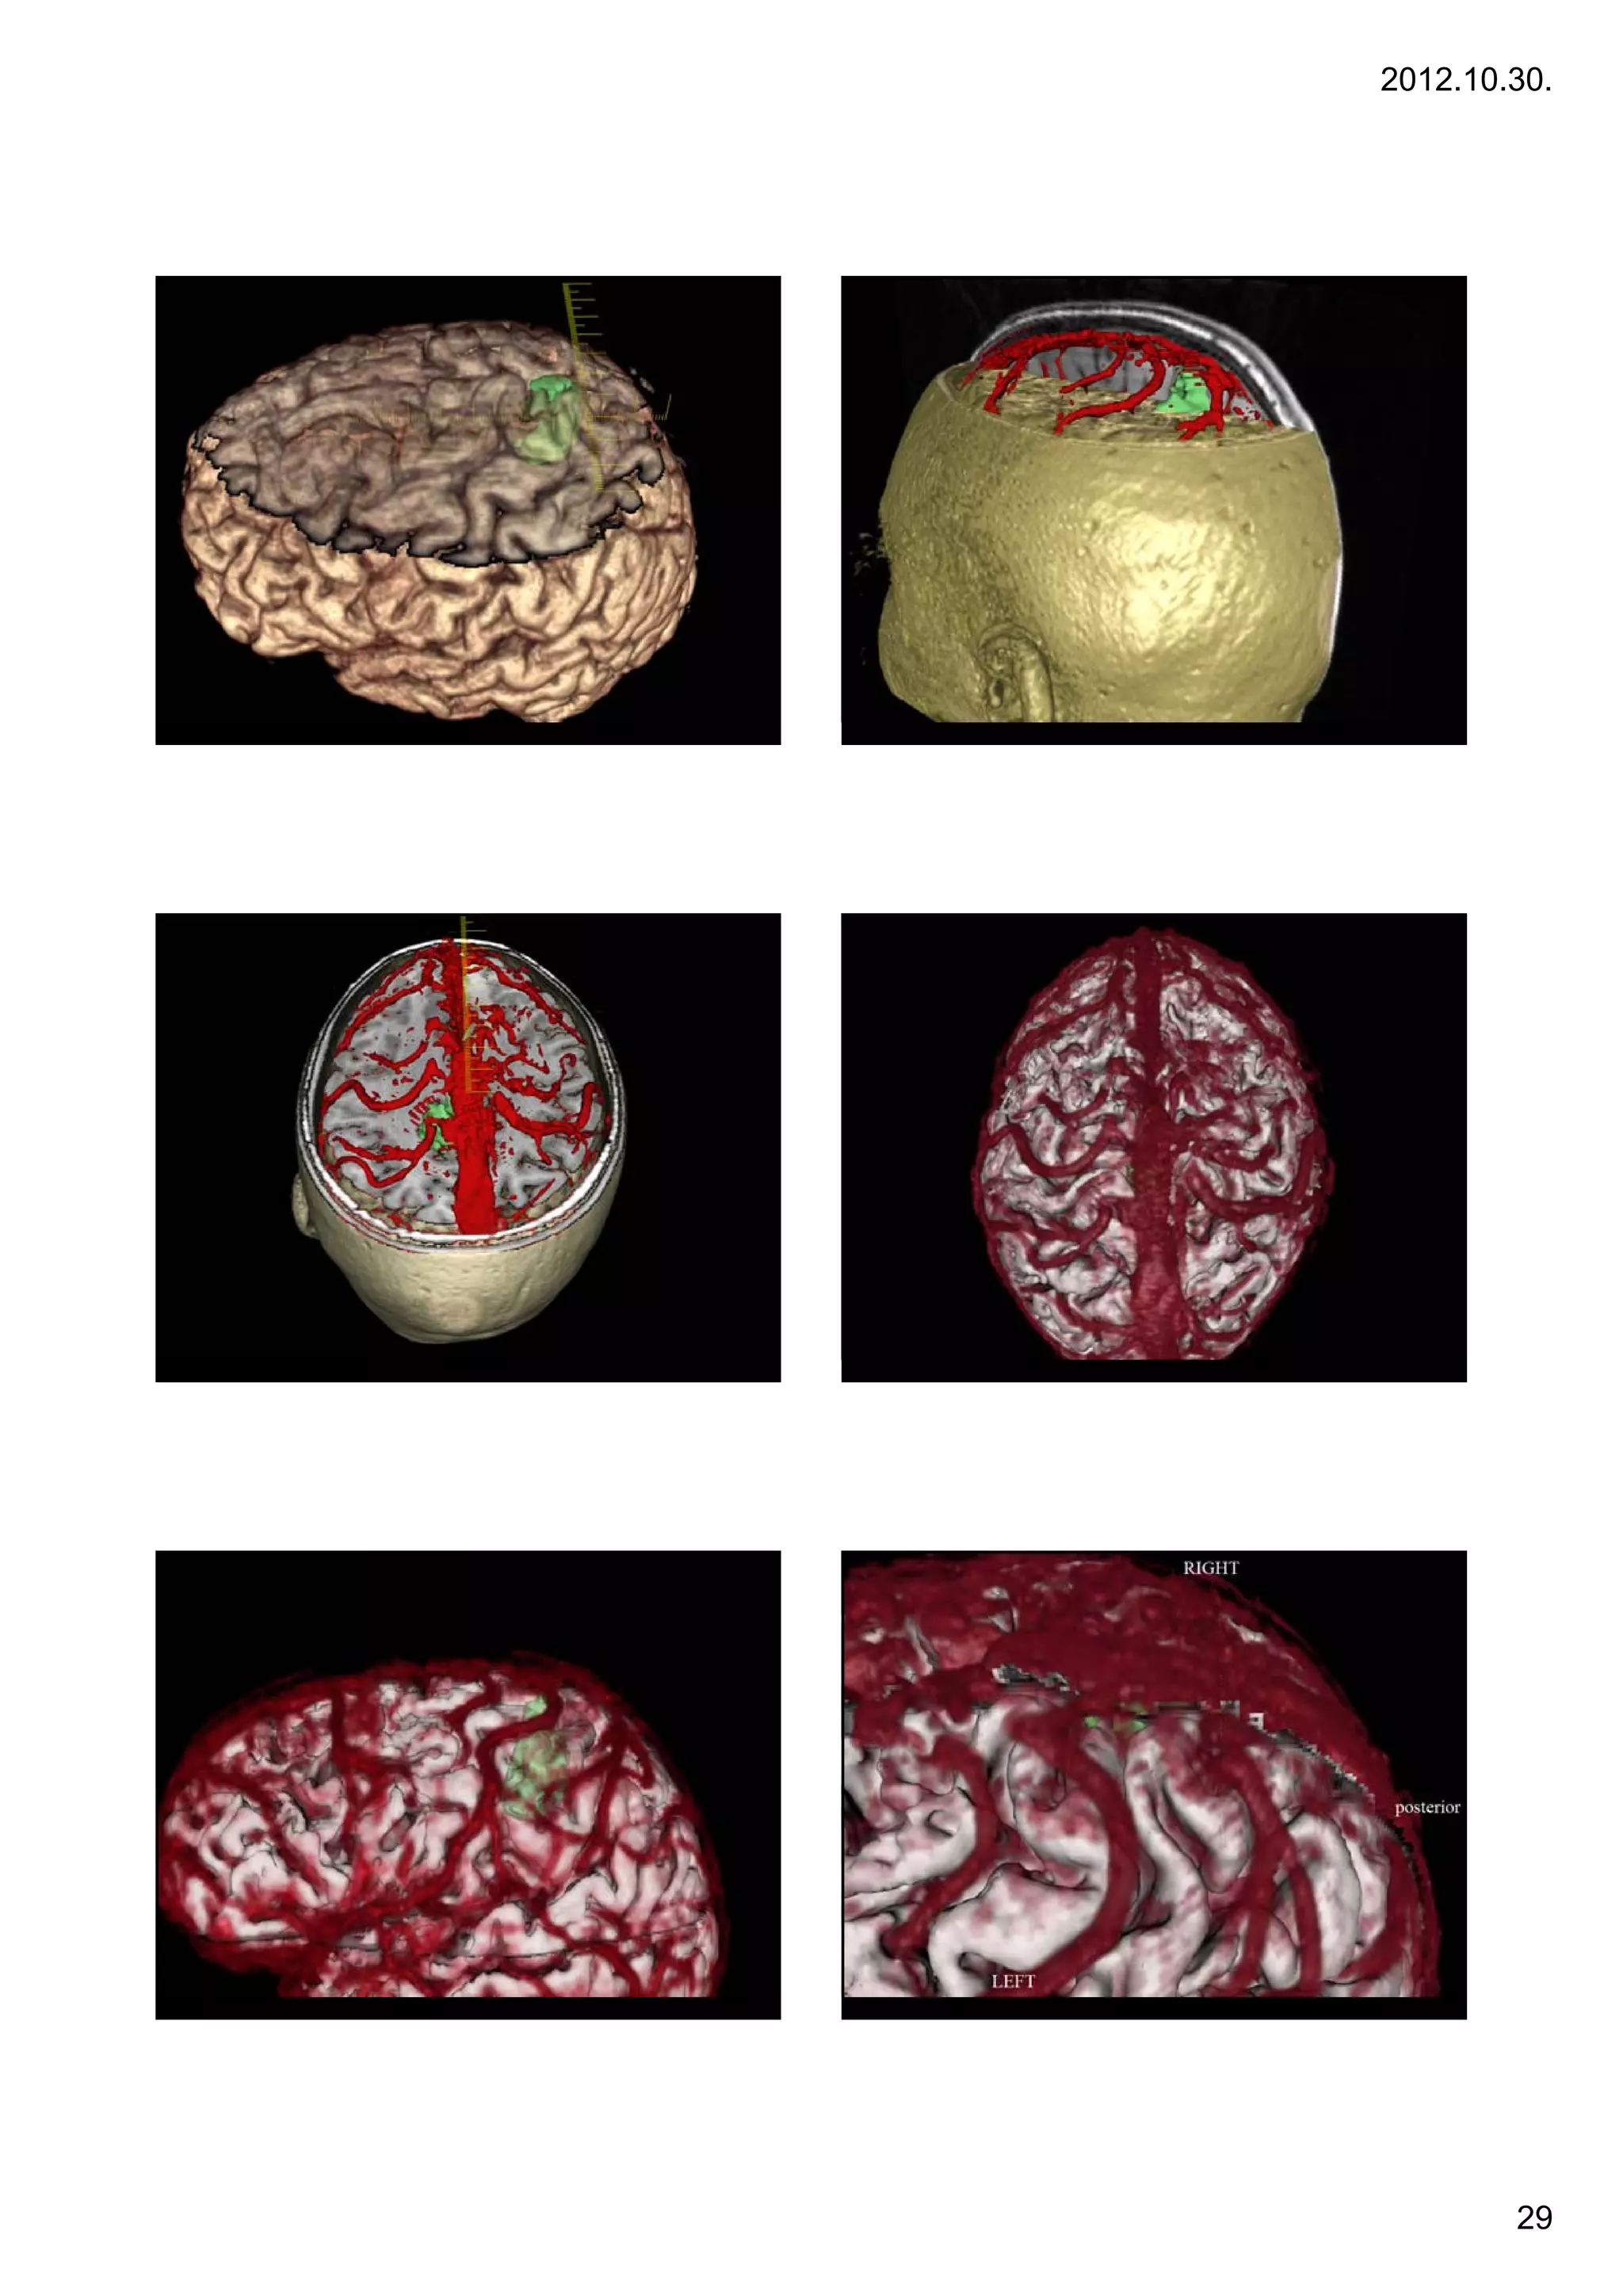

Képregisztrációk (CT + DTI)

Case 8

8.

CT + ADC map                                   CT + colorized FA map